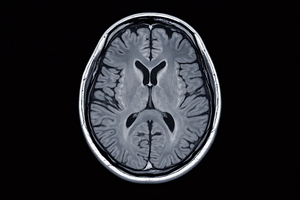

모야모야병 환자에서 뇌졸중 발생 위험이 높다고 알려진 가운데 영상학적 혈관 신호로 이를 예측할 수 있다는 연구결과가 나왔다. 경희대병원 신경외과 유지욱 교수팀은 혈관을 덩굴처럼 둘러싼 형태의 조영증강 신호인 'Ivy Sign'이 넓을수록 뇌졸중 위험이 모두 증가했다고 뇌졸중·혈관 · ...